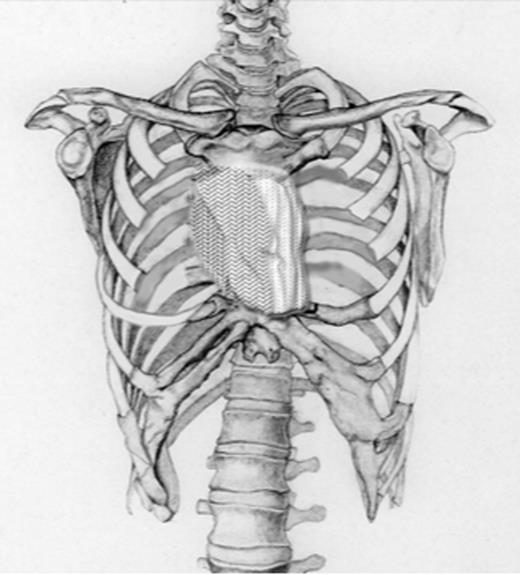

Schematic drawing of the size of the defect after radical excision followed by placing steel wires through the stenal ends.

This picture shows the size of the defect in the patient after radical resection, which was 6.5 centimetres. Consequently, steel wires were placed through the sternal ends and the left sternoclavicular joint and a polypropylene mesh was place on the surface of the defect.